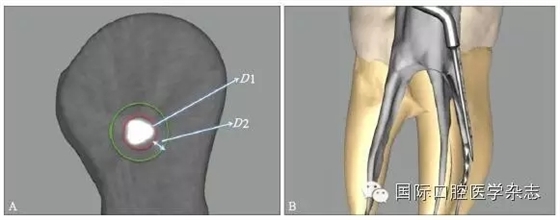

目前,對于分離器械周圍牙本質(zhì)厚度的評估以及取出后殘余牙本質(zhì)厚度的預(yù)測主要需借助影像學(xué)檢查,例如根尖片、錐形束CT(cone beamcomputed tomography,CBCT)圖像等。傳統(tǒng)的平行投照的根尖片無法反映三維立體結(jié)構(gòu),且往往存在解剖結(jié)構(gòu)影像的重疊,不利于臨床判斷,具有一定的局限性。多位學(xué)者[10]的研究表明:平行投照的根尖片會高估實(shí)際的牙本質(zhì)壁的厚度。一些學(xué)者[11-12]的研究表明:當(dāng)分離器械位于上頜第一磨牙近中根管時,采用成角投照(21°)的拍攝技術(shù)與平行投照技術(shù)得到的X線片相比,能更準(zhǔn)確地評估牙本質(zhì)的厚度,為分離器械取出與否提供指導(dǎo)(圖4)。近年來,CBCT在牙髓病學(xué)中的應(yīng)用越來越廣泛,由于CBCT能清楚地反映牙及牙根周圍組織的三維立體結(jié)構(gòu),為牙本質(zhì)厚度的評估與預(yù)測提供了可行性(圖5);因此,CBCT在器械分離的病例術(shù)前風(fēng)險評估方面具有較好的應(yīng)用前景。

圖 5 使用CBCT評估分離器械周圍牙本質(zhì)厚度

為了盡可能地減少牙本質(zhì)的損失量,應(yīng)當(dāng)根據(jù)分離器械的斷端直徑選擇合適尺寸的超聲工作尖或者環(huán)鉆,然后根據(jù)計算公式:D≥D1+D2(×2)計算選擇合適型號的GG鉆,創(chuàng)造相應(yīng)大小的平臺,為后續(xù)分離器械的取出建立直線通路。其中,D為GG鉆的理論最小直徑,D1為分離器械的末端直徑,D2為超聲工作尖的直徑或環(huán)鉆壁的厚度。當(dāng)超聲工作尖僅在分離器械一側(cè)運(yùn)動,則公式中D2不需要(×2)(圖6)。具體要點(diǎn)詳見4.1。

A:D1為分離器械的末端直徑,D2為超聲工作尖的直徑或環(huán)鉆壁的厚度;B:當(dāng)超聲工作尖僅在分離器械一側(cè)運(yùn)動,則公式中D2不需要(×2)。

圖 6 GG鉆理論最小直徑的計算